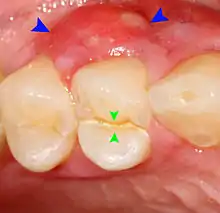

Decay (green) with apical abscess (blue)

The periodontal ligament becomes inflamed and there may be pain when biting or tapping on the tooth. On an X-ray, bone resorption appears as a radiolucent area around the end of the root, although this does not manifest immediately.[10]: 228 Acute apical periodontitis is characterized by well-localized, spontaneous, persistent, moderate to severe pain.[6]: 125–135 The alveolar process may be tender to palpation over the roots. The tooth may be raised in the socket and feel more prominent than the adjacent teeth.[6]: 125–135

Apical periodontitis is acute or chronic inflammation around the apex of a tooth caused by an immune response to bacteria within an infected pulp.[20] It does not occur because of pulp necrosis, meaning that a tooth that tests as if it's alive (vital) may cause apical periodontitis, and a pulp which has become non-vital due to a sterile, non-infectious processes (such as trauma) may not cause any apical periodontitis.[10]: 225 Bacterial cytotoxins reach the region around the roots of the tooth via the apical foramina and lateral canals, causing vasodilation, sensitization of nerves, osteolysis (bone resorption) and potentially abscess or cyst formation.[10]: 228